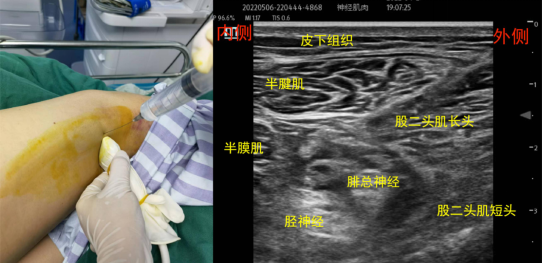

解剖关键点:腘窝皮肤褶皱上方约6cm处、底-大收肌和股动脉股静脉、内上-半膜肌、内上表面-半腱肌、外上表面-股二头肌长头

扫查方法:将探头放置在腘窝皮肤褶皱上方,通过腘动脉定位,坐骨神经位于腘动脉上方偏外侧的圆形高回声。向远端滑动探头,可见坐骨神经分为内侧胫神经和外侧腓总神经。

经验技巧:在此部位坐骨神经由深部向浅部走行,可将超声探头的柄部向身体头侧倾斜,让超声束向尾端略倾斜,坐骨神经显示更清晰。腘窝上入路是最简单的方法,因为该处坐骨神经表浅,又有腘窝动脉做参考,比较容易找到。

穿刺方法:平面内法(不建议平面外法),大腿外侧进针,局麻药注入胫神经和腓总神经的汇合处,观察药液是否在神经旁鞘内和整个神经束外扩散。